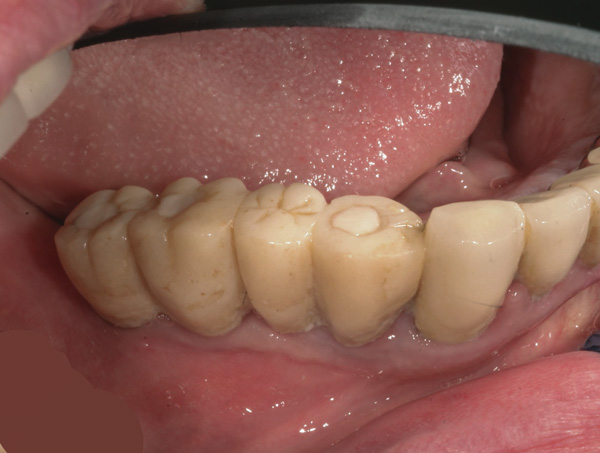

Background: This patient had a failing maxillary dentition and refused to wear a removable prosthesis. A staged approach was employed to retain some of his natural tooth abutments, and recession was noticed at the time of the impression for the second group of implants. Figure 1 shows the patient following insertion of the first set of implant custom abutments; the adjacent natural teeth are still present to support the provisional bridge. Seven months later, as shown in Figure 2, those first-stage custom abutments exhibited evidence of 1 mm to 3 mm of recession.

Figure 1  Patient following insertion of first set of implant custom abutments.

Figure 1

Figure 2 After 7 months, the first-stage custom abutments exhibited evidence of 1 mm to 3 mm of recession.

Figure 2